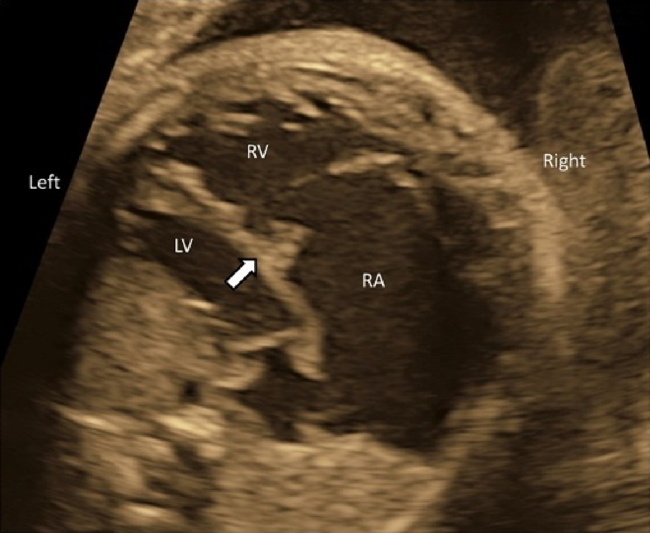

(2) 4CV

- The laterality of the left and the right ventricles can be determined using the 4CV. The right ventricle is characterized by the moderator bands within its cavity.

- The 4CV demonstrates whether the ventricles contract well or not. Reduced left ventricular contraction may indicate severe aortic stenosis, while reduced contraction of the right ventricle could suggest premature constriction of the ductus arteriosus. When both ventricles are less contractile, myocarditis or cardiomyopathy may be the reason.

- Whether the AV valves are competent should be determined using color Doppler echocardiography in the 4CV. If moderate to severe AV valve regurgitation were noted, the fetus would likely have structural abnormalities or dysfunction of the heart.

- The direction of the blood flow through the foramen ovale should be assessed using color Doppler echocardiography in the 4CV. Finding a stream from the left to the right, structural abnormalities, such as obstruction within the left heart, should be sought. Finding no blood flow across the inter-atrial septum, premature constriction of the foramen ovale might be the case.

- The midline of the heart should be scrutinized. An AV septal defect or a large ventricular septal defect can be diagnosed using tomographic ultrasound scans. A small defect would require color Doppler echocardiography.

- The connection of the left and the right pulmonary veins to the left atrium should be confirmed by tomographic ultrasound, color Doppler ultrasound, and pulmonary venous pulsed Doppler waveforms. The pulsed Doppler waveforms of the pulmonary veins are normally bimodal. The waveforms would be unimodal or flat in fetuses with total anomalous pulmonary venous return or pulmonary venous stenosis. Also, the former should be suspected when the distance between the posterior wall of the left atrium and the descending aorta is greater than normal.55)

- The 4CV is used to detect an abnormal mass in the heart.

- The 4CV illustrates collection of pericardial fluid or pleural effusion.